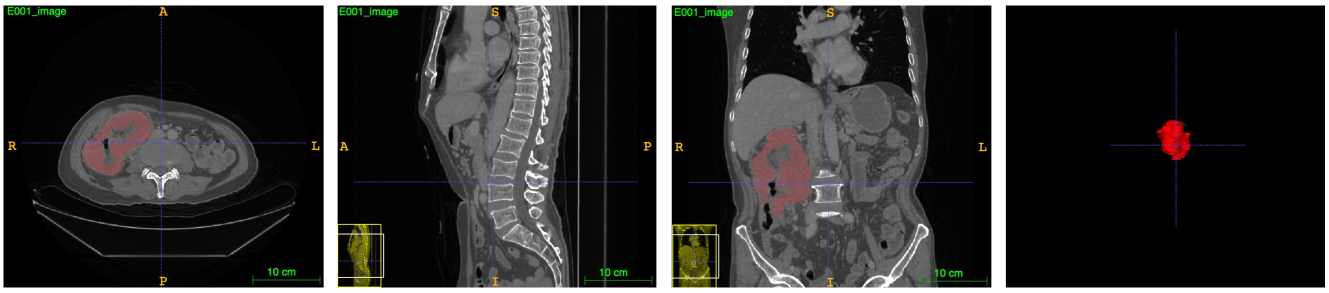

Necessity for CRC-500 Dataset Colorectal cancer (CRC) is the third most common cancer worldwide among men and women, the second leading cause of death related to cancer, and the primary cause of death in gastrointestinal cancer [4]. Using deep learning methods to detect the cancer region can assist doctors in making more accurate diagnoses. However, as shown in Table 1, the current 3D colorectal cancer segmentation datasets are small in size. Moreover, only the MSD dataset is publicly available, but it lacks data on rectal cancer. To facilitate research in the 3D colorectal cancer segmentation field, we contribute a new large-scale dataset (named CRC-500). This dataset consists of 500 3D colorectal volumes with corresponding precise annotations from experts. Fig. 1 presents examples in 2D format from our proposed CRC-500 dataset. The details of our CRC-500 will be discussed below.

Refer to caption

Figure 1: The data visualization for CRC-500 dataset.